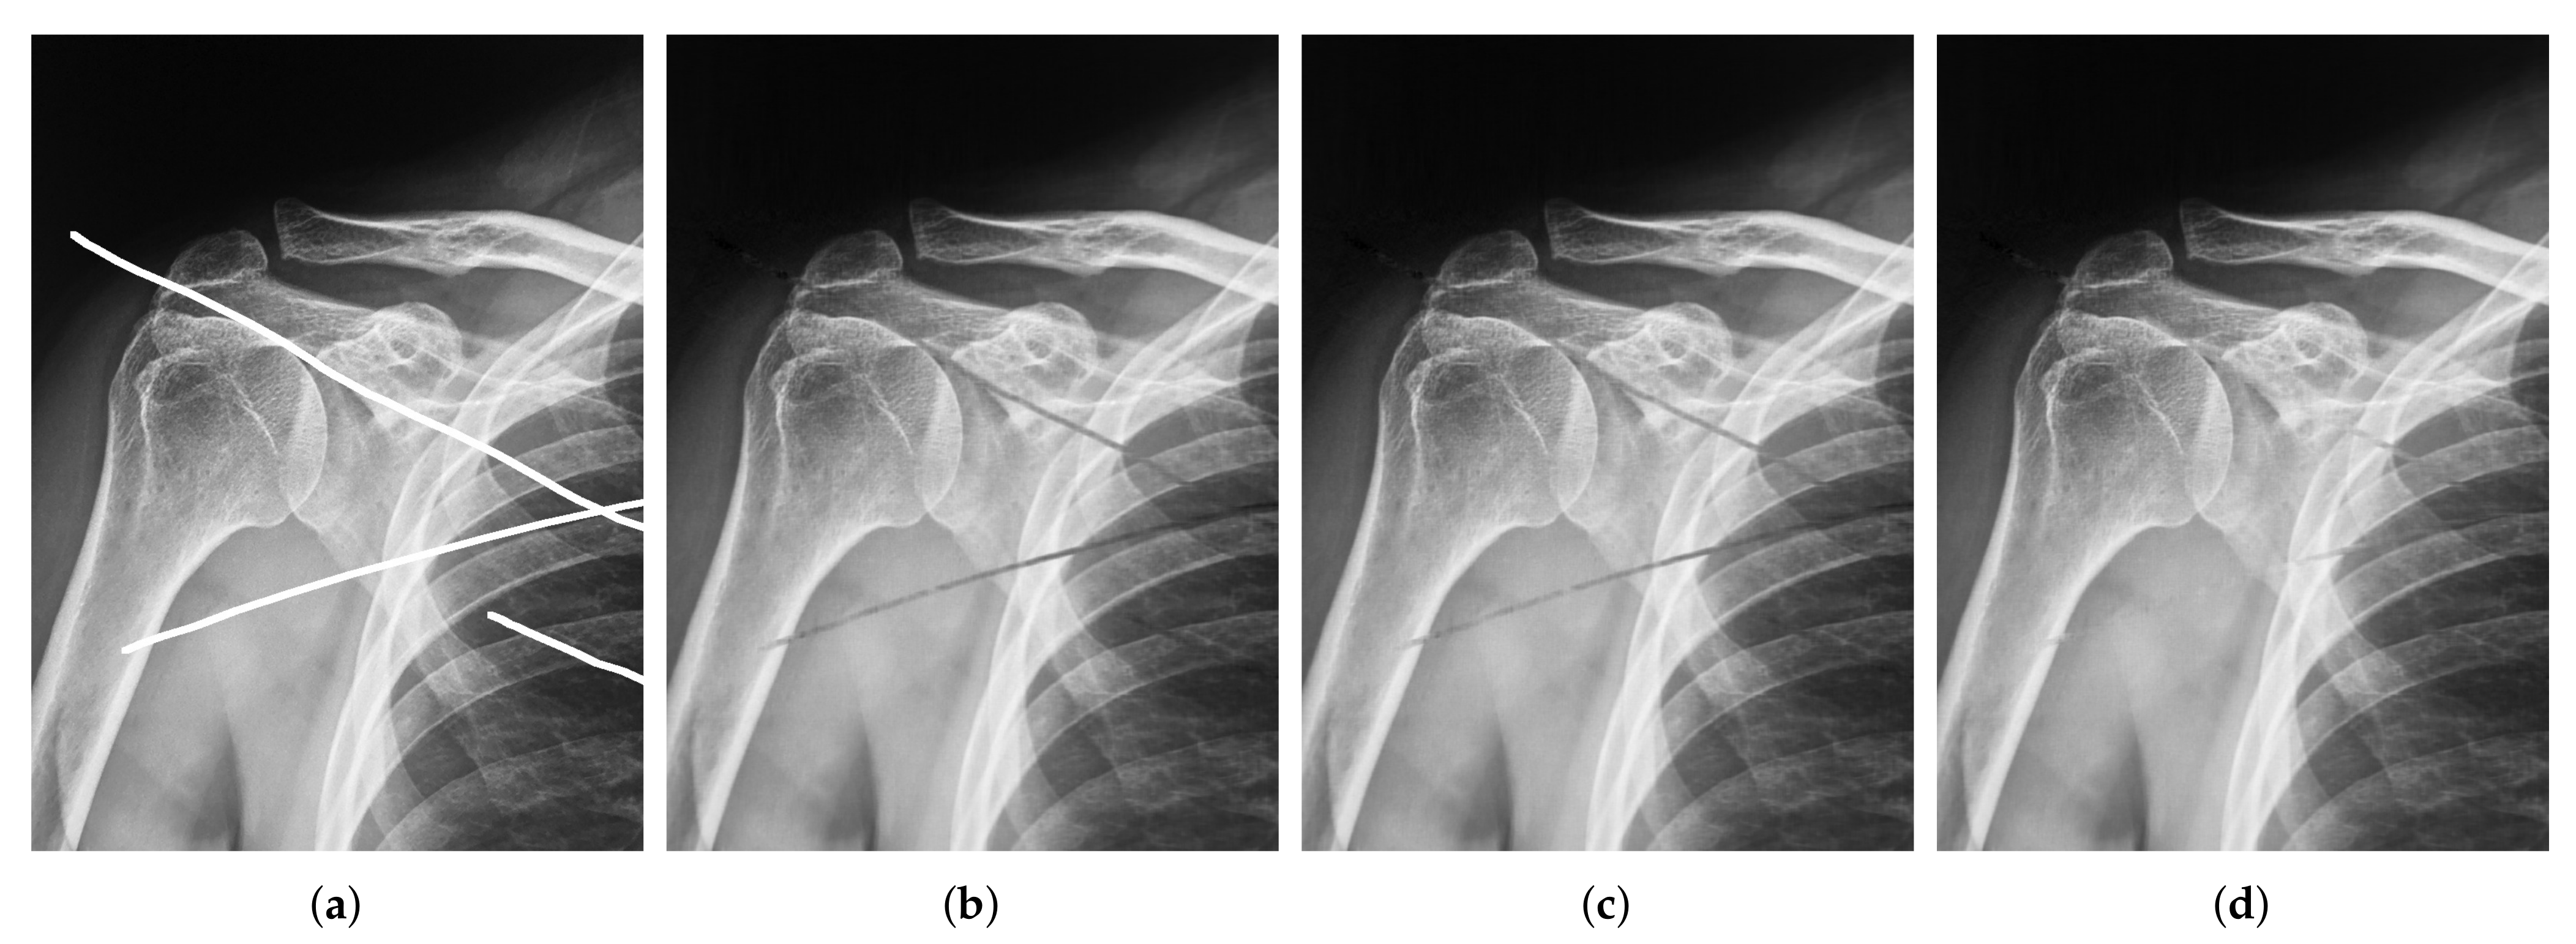

| Image Size | Image Size | |||

|---|---|---|---|---|

| SNR | SSIM | SNR | SSIM | |

| Algorithm 1 | 19.8276 | 0.9378 | 25.7210 | 0.9363 |

| Algorithm 2 | 20.4704 | 0.9402 | 26.2362 | 0.9373 |

| Algorithm 5 | 22.9158 | 0.9477 | 27.6581 | 0.9400 |